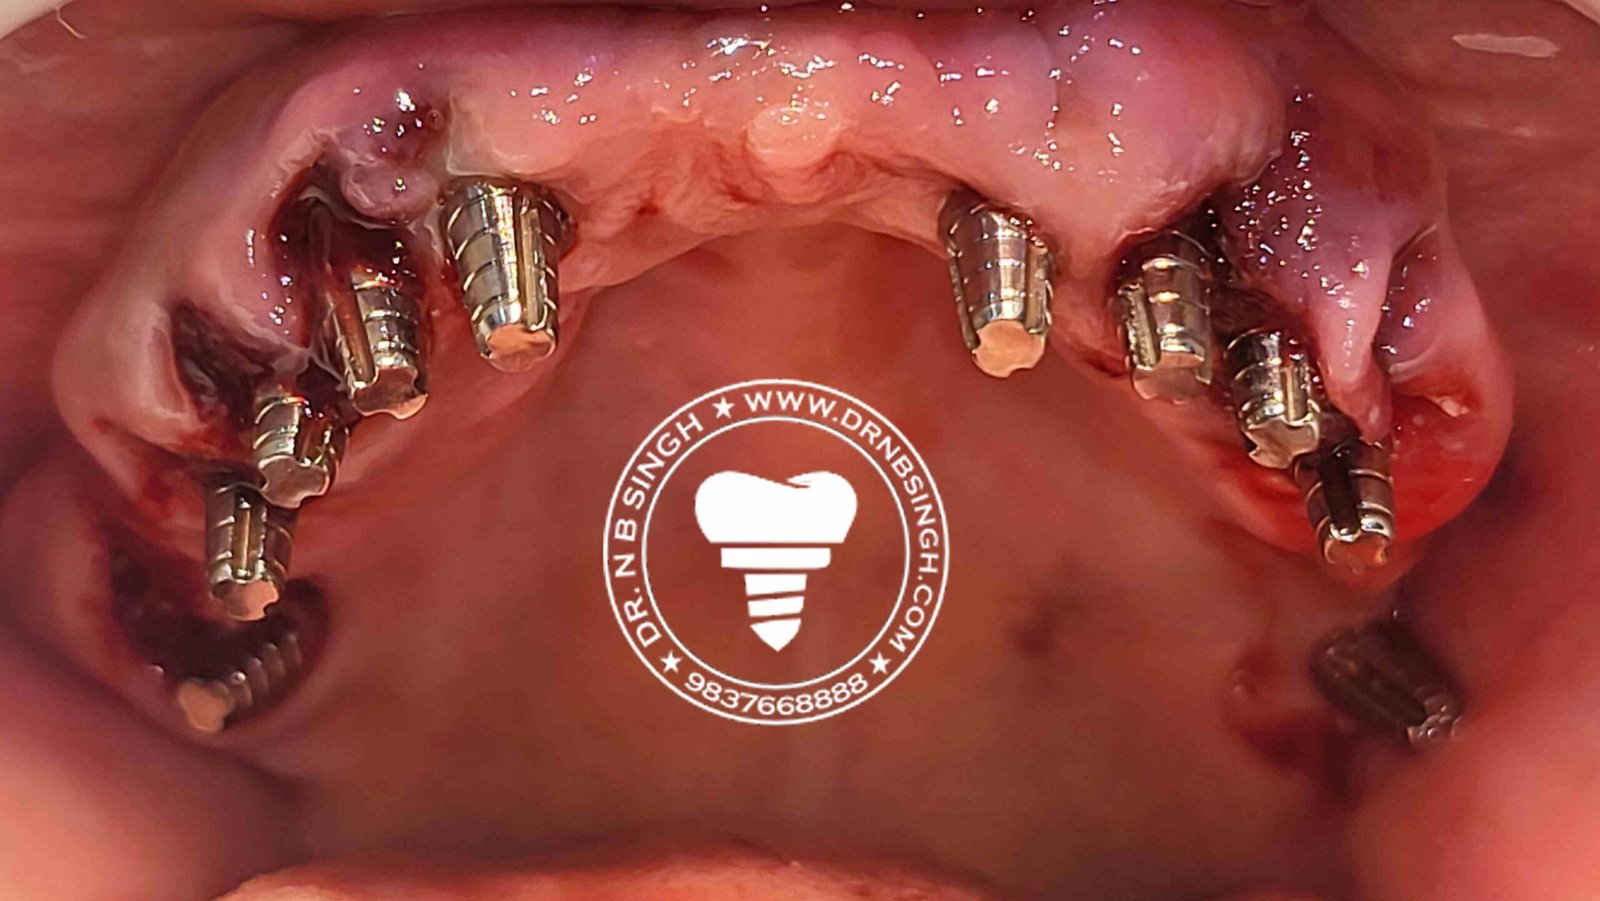

1002 Basal Full Mouth Implants Case Rubeena 2

1002 basal implant full mouth case rub 4